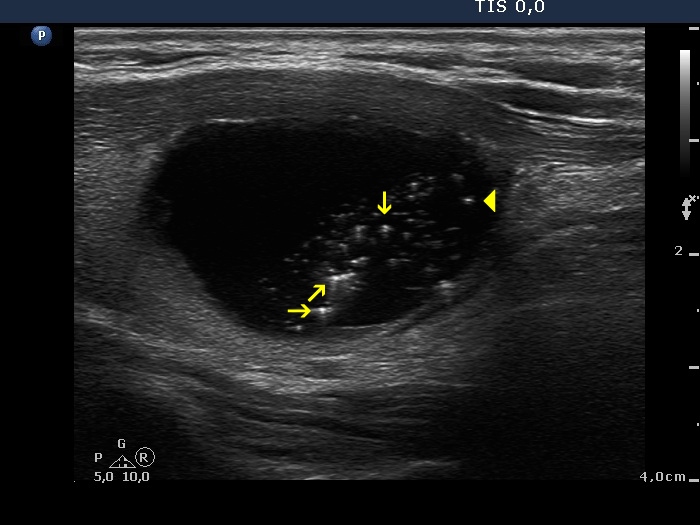

Intranodular hyperechogenic figures - case 624 (ultrasonographic picture 3b)

Right lobe, longitudinal view. Yellow arrows point to comet-tail artifacts having a dorsal tail while the arrowhead shows a comet-tail artifact without a tail.